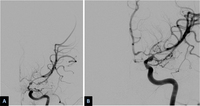

Severe vasospasm of distal left internal carotid artery and proximal middle and anterior cerebral arteries before (A) and after (B) intra-arterial infusion of nicardipine and transluminal balloon angioplasty

Courtesy of Dr Salah Keyrouz; used with permission